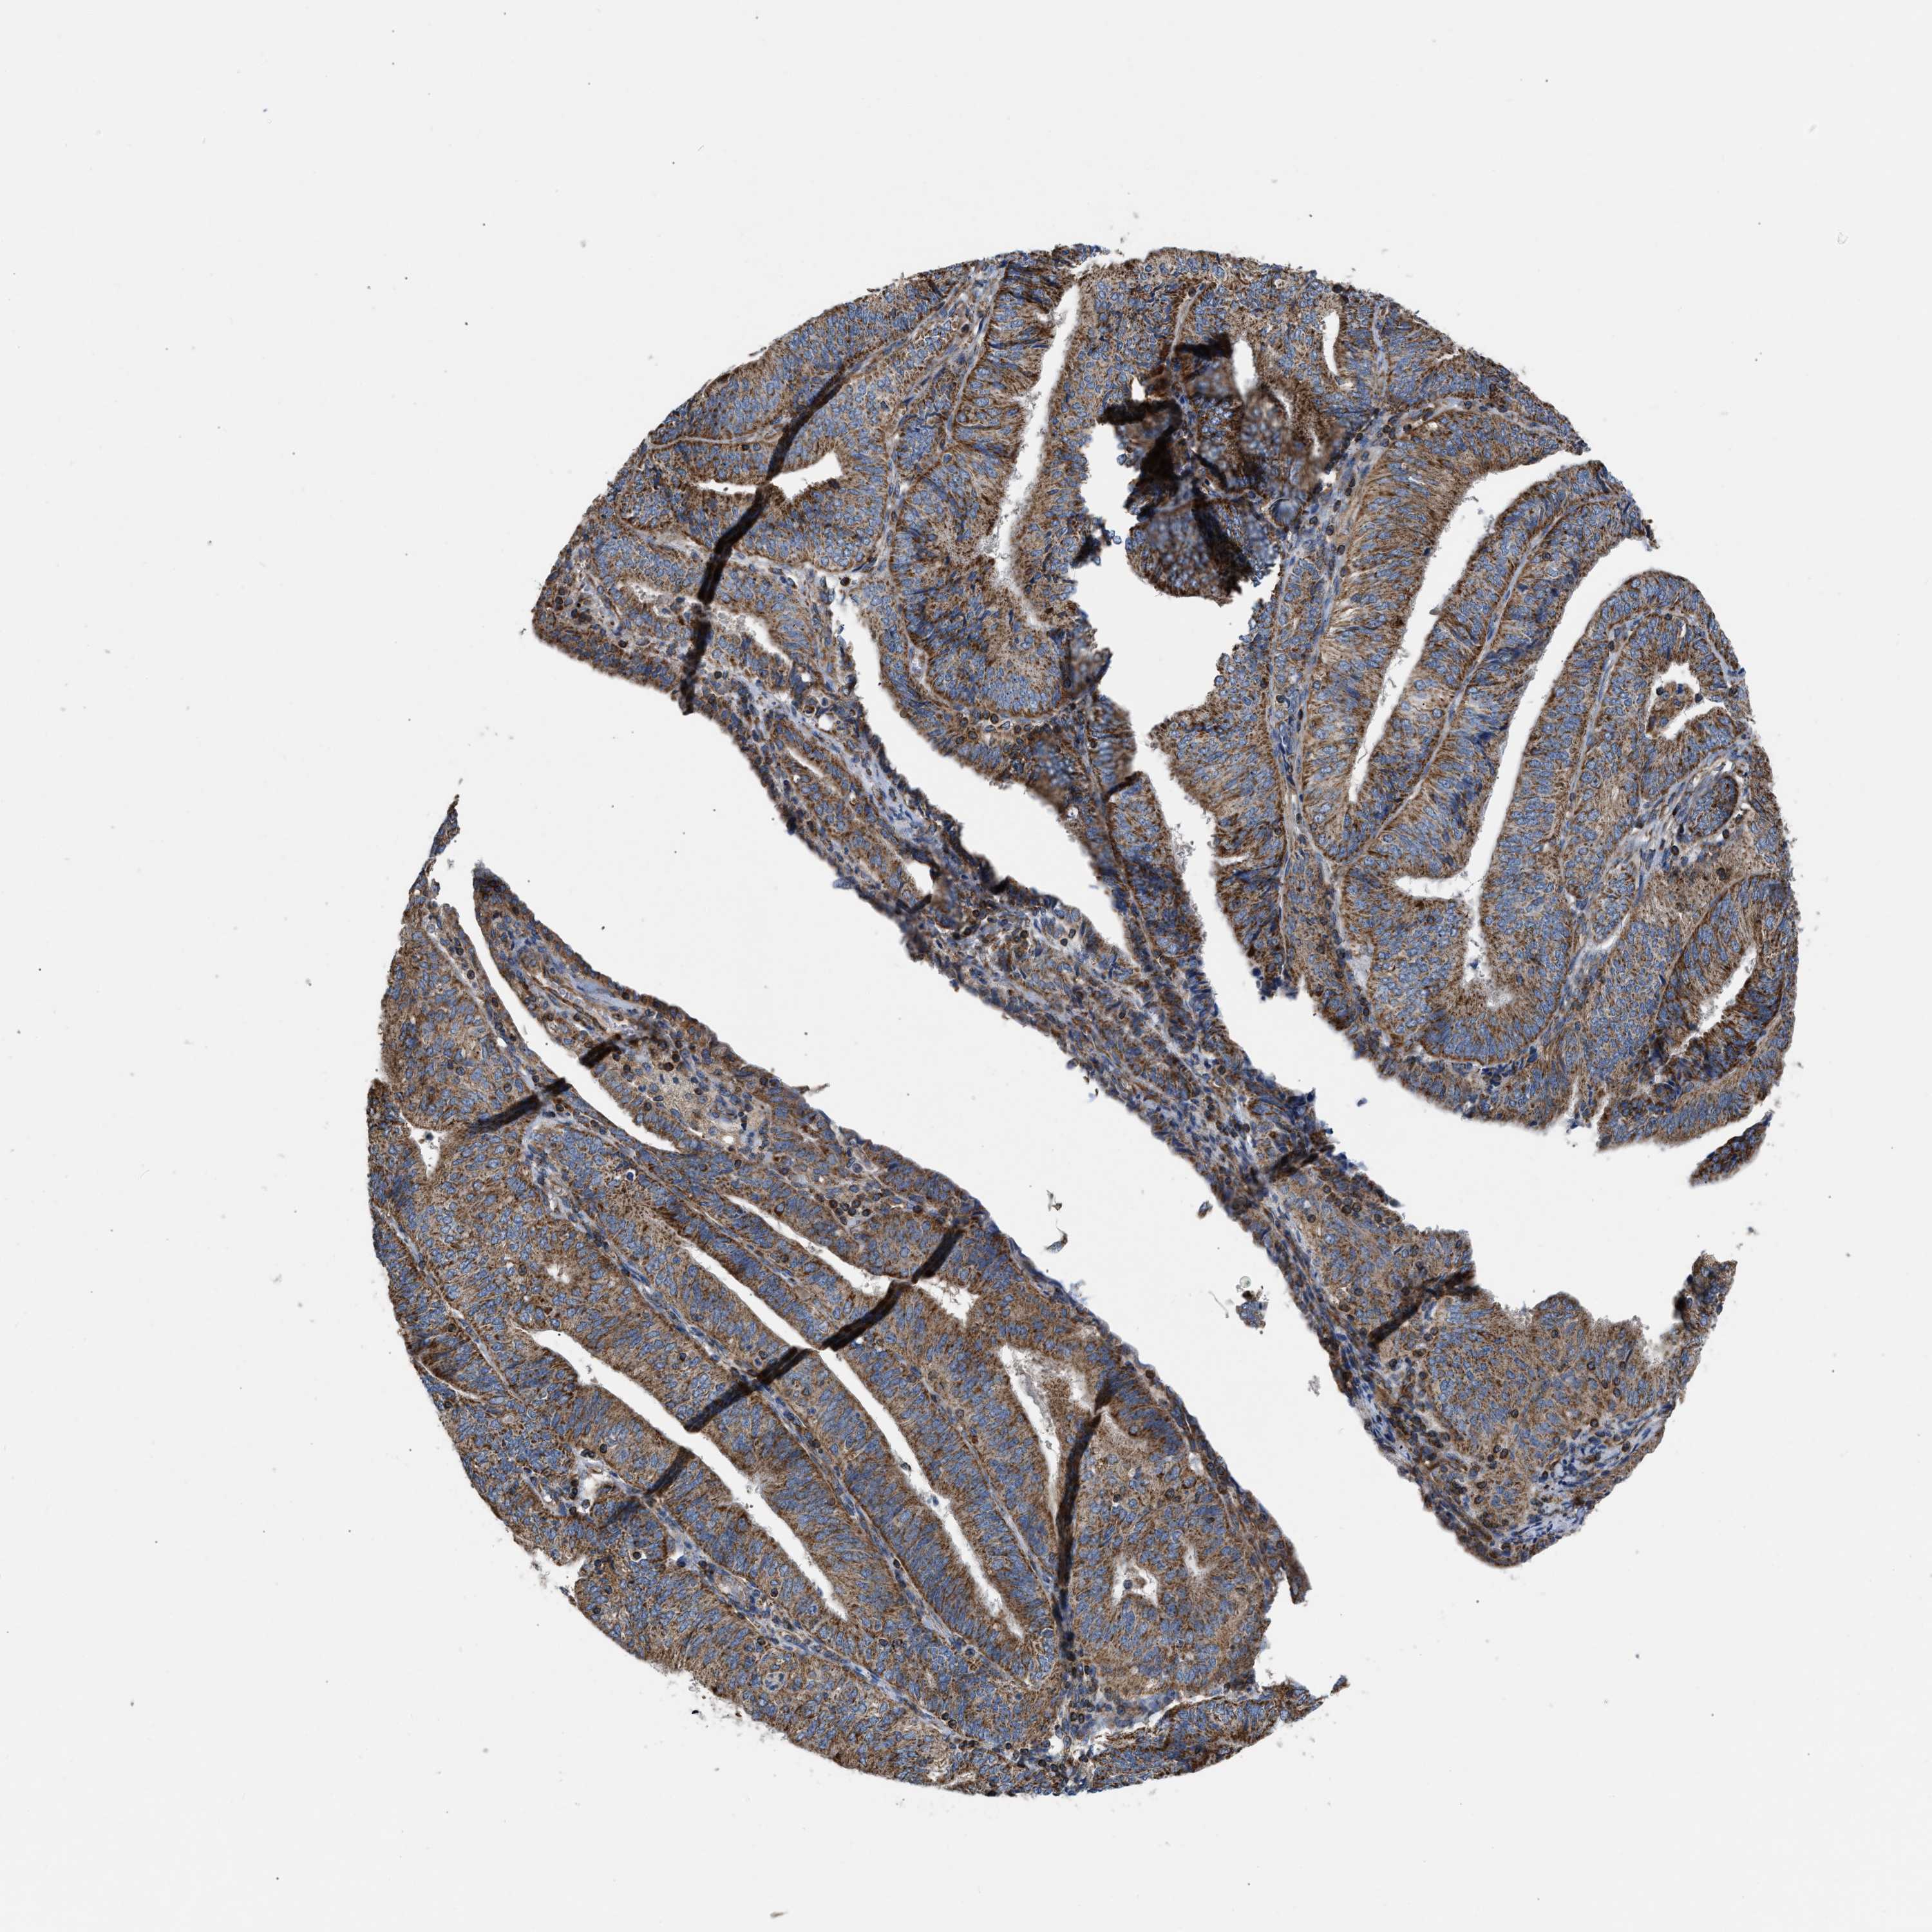

ENDOMETRIAL CANCER - Protein expressioni

A mouse-over function shows sample information and annotation data. Click on an image to view it in a full screen mode. Samples can be filtered based on level of antibody staining by selecting one or several of the following categories: high, medium, low and not detected. The assay and annotation is described here.

Note that samples used for immunohistochemistry by the Human Protein Atlas do not correspond to samples in the TCGA dataset.

Antibody stainingi

Antibody staining in the annotated cell types in the current human tissue is reported as not detected, low, medium, or high, based on conventional immunohistochemistry profiling in selected tissues. This score is based on the combination of the staining intensity and fraction of stained cells.

Each image is clickable and will lead to virtual microscopy that enables deeper exploration of all samples and also displays staining intensity scores, fraction scores and subcellular localization as well as patient and tissue information for each sample.

Antibody HPA003279

Antibody HPA003360

Antibody CAB019303